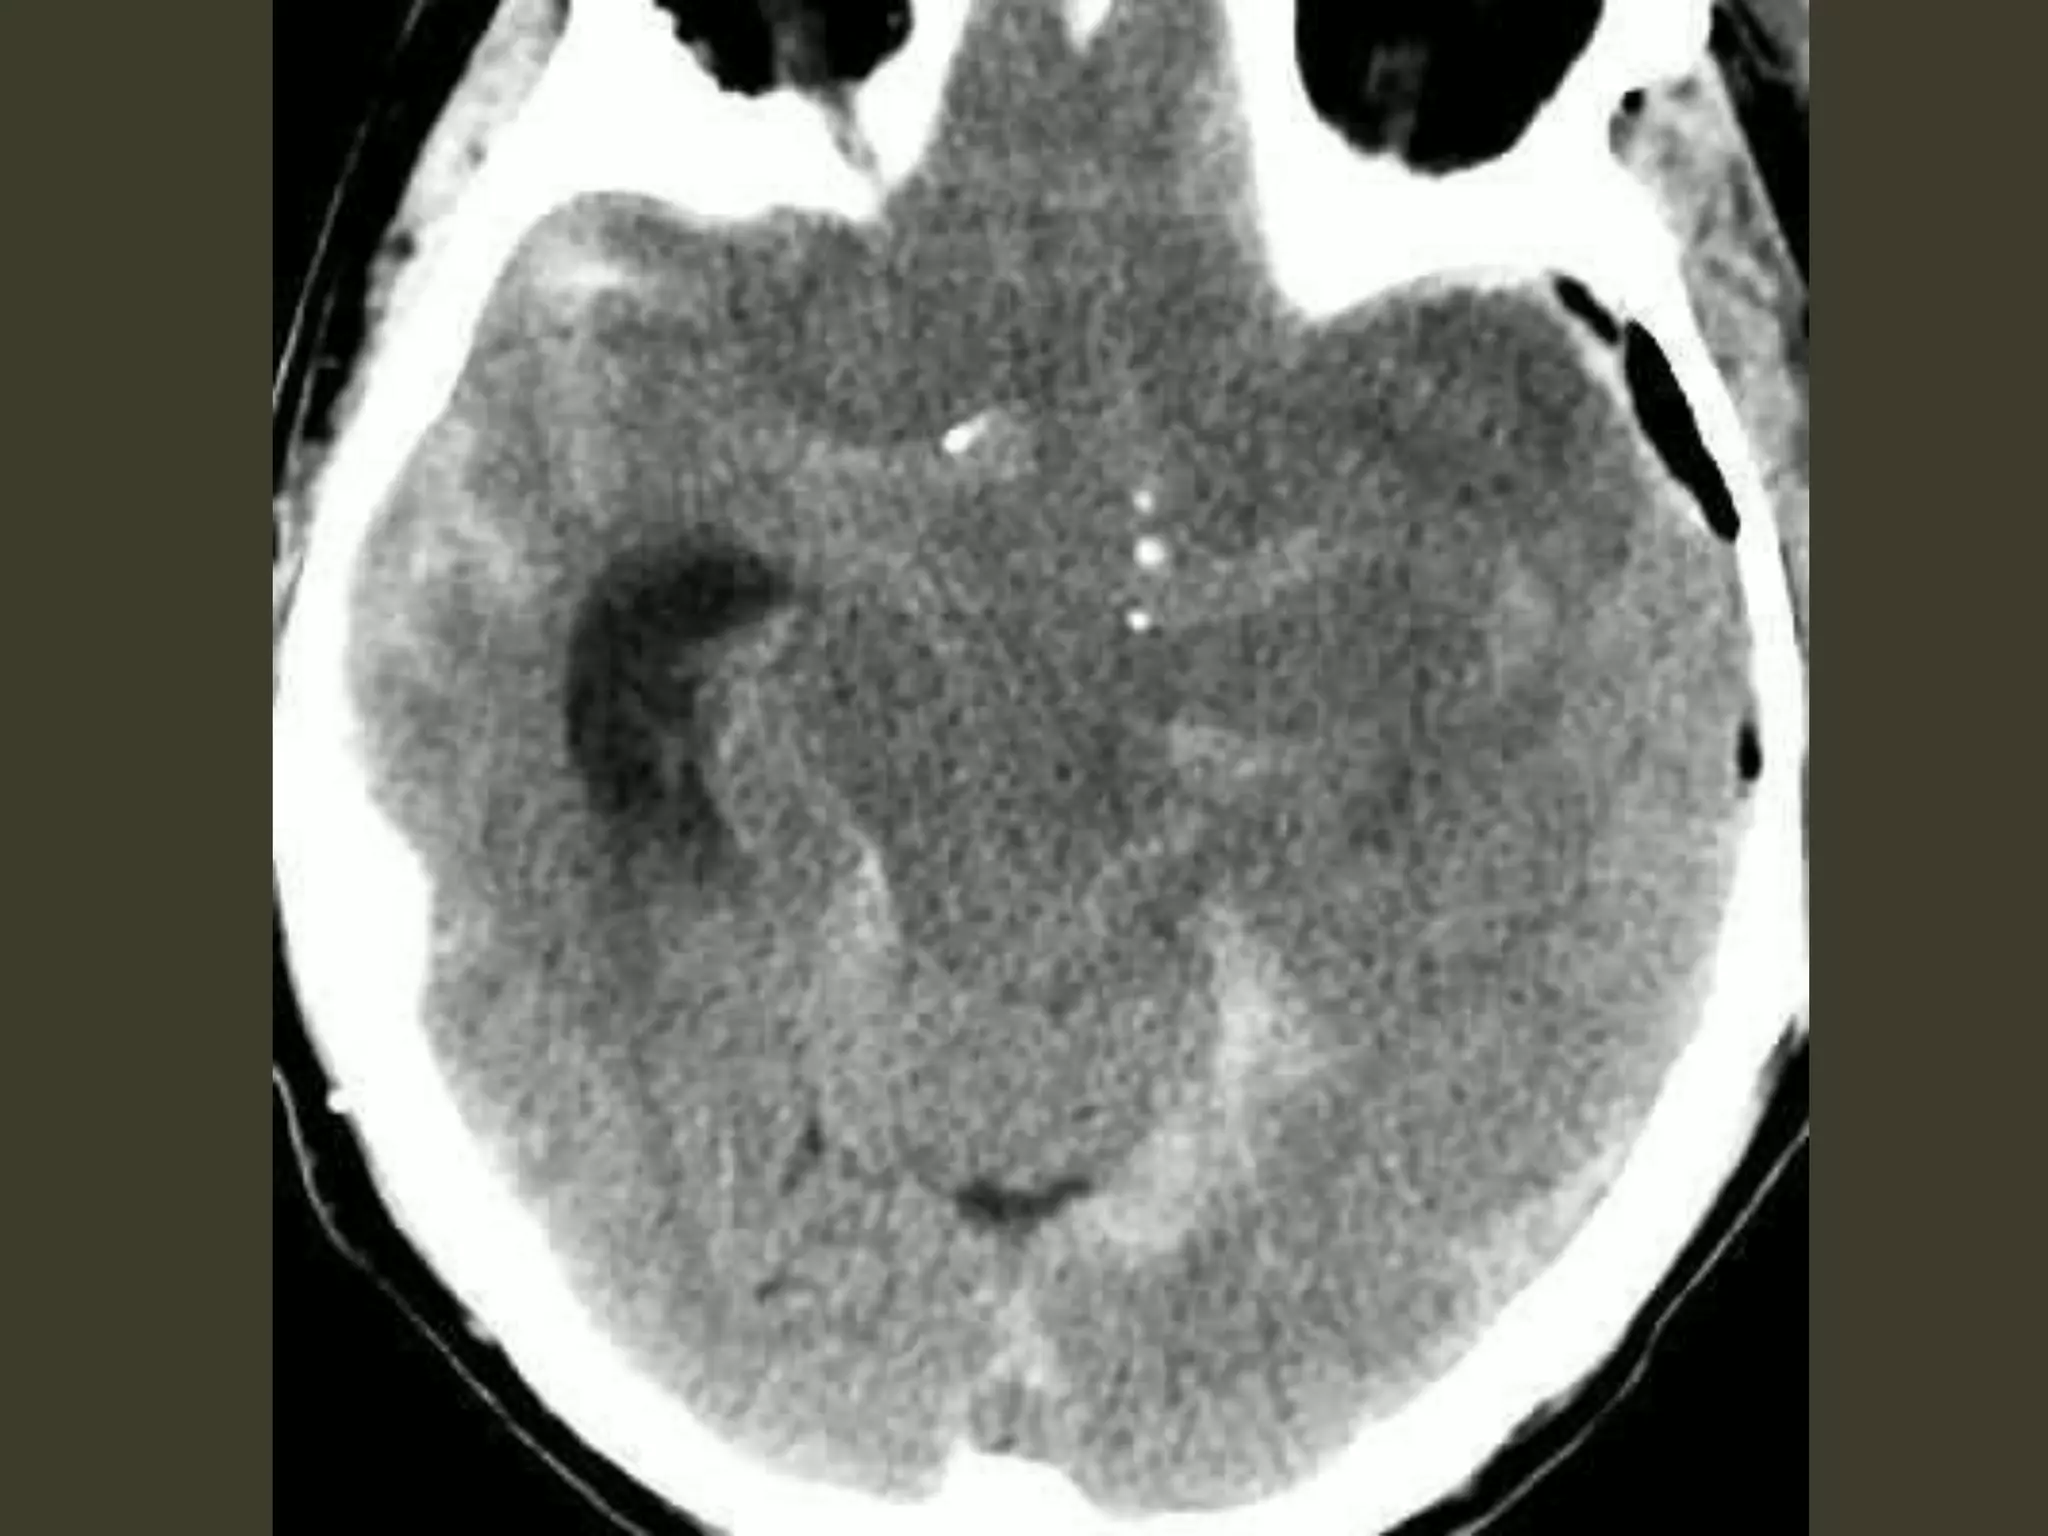

Subfalcine herniation: imaging

Axial and coronal images show that

•cingulate gyrus

•anterior cerebral artery (ACA)

•internal cerebral vein (ICV)

are pushed from one side to the other under the

falx cerebri.

The ipsilateral ventricle appears compressed

and displaced across the midline

Complications

• unilateral obstructive hydrocephalus

– foramen of Monro occlusion

• Periventricular hypodensity with "blurred"

margins of the lateral ventricle

– Fluid accumulates in the periventricular white

matter

• When severe, the herniating ACA can be

pinned against the inferior "free" margin of

the falx cerebri

🡪 secondary infarction of the cingulate gyrus